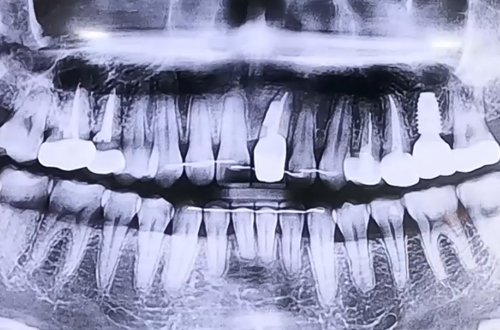

임플란트와 함께 앞니 치료 진행한 사례

치료 유형 어금니 임플란트, 앞니 충치 치료

본래 저희 병원에서 어금니 임플란트 치료를 진행하고 계셨던 환자분으로 치아와 잇몸의 상태 등 여러 조건이 양호해서 어렵지 않게 임플란트 하고 계셨던 분입니다.

임플란트 식립 후 굳을 때까지 4개월을 기다리면서 경과를 보기 위해 내원해 검사를 받게 되는데요.

검진을 위해 오신 환자분께서, 얼마전부터 앞니에 염증이 생기고 붓는다고 앞니 검사를 해 보고 싶다고 요청을 해 주셨습니다.

그래서 불편해하시는 앞니를 정밀하게 검사해본 결과, 이전에 보철치료를 했던 앞니 부분의 안쪽에 충치가 발생했고, 그 충치를 중심으로 겉으로 염증이 발생한 상태로 보였습니다.

이렇게 안쪽에 생긴 염증이 바깥쪽으로 빠져나갈 통로가 없어서 잇몸이 붓고 터지는 것인데요.

치아는 그대로 살리면서 안쪽 충치를 치료한 뒤 염증을 깨끗이 긁어내고 잇몸을 닫는 치주 수술을 진행해드리며 임플란트 역시 함께 마무리 해 드렸던 케이스입니다.